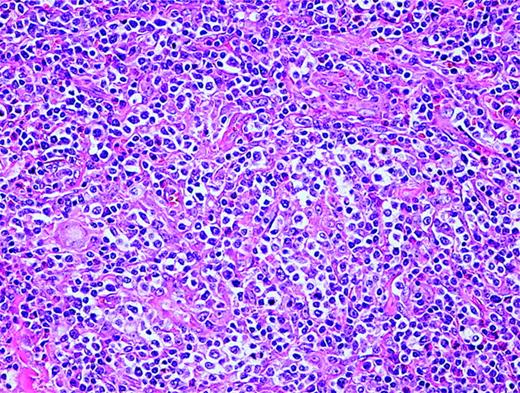

Anaplastic large-cell lymphoma. Infiltrate is composed of large transformed lymphocytes, including hallmark cells with kidney-shaped nuclei.

Pathology

The morphology of ALCL, systemic type, consists of large lymphoid cells with pleomorphic or multiple prominent nuclei and abundant cytoplasm (Figure 3). Tumor cells grow in a cohesive pattern, and there is often sinusoidal spread in the lymph nodes. Tumor cells express CD30 and either T cell or no specific lineage antigens (null cell).